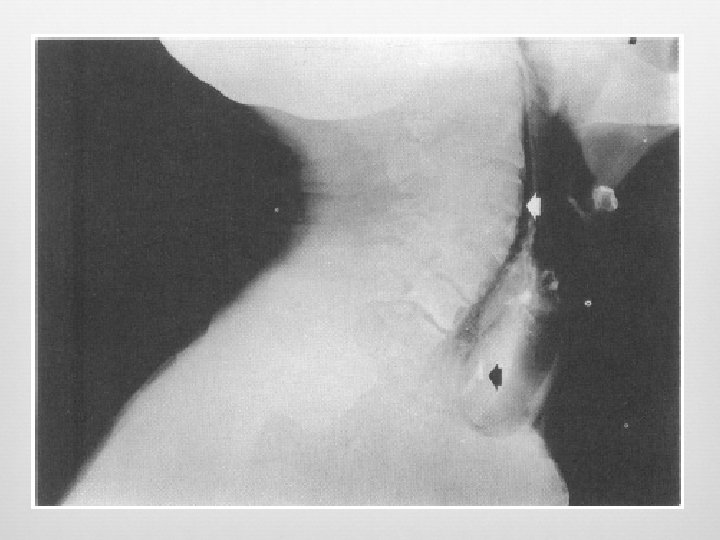

Retropharyngeal Infection Widened retropharyngeal space C 2 – 7 mm or C 6 – 14 mm (kids) C 6 – 22 mm (adults) Reversal of normal cervical lordosis Foreign body Air-fluid level Gas

False Pre-vertebral Swelling Oblique lateral Neck flexion Crying